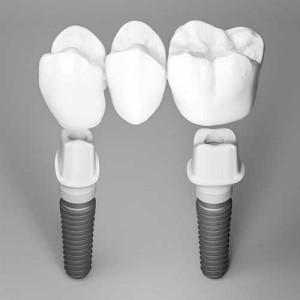

Treatments using dental implants to replace missing teeth are effective and predictable. However, with the ever-growing popularity of implant treatments and...